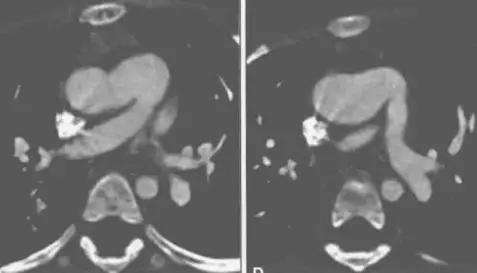

5.CTMR表现

I型:可见缺损紧邻半月瓣的上部层面,升主动脉左后壁与肺动脉主干的右前壁相连通,二者之间有血流信号或造影剂通过

II型:缺损位于升主动脉的远端,此型易与窗型动脉导管未闭相混淆,当PDA位于降主动脉和肺动脉之间,在图像上表现为缺损的前方是肺动脉,后方是(降)主动脉,而APSD恰好相反,APSD的右前方是升主动脉,而左后方是主肺动脉。

III型:缺损较大,累及升主动脉的全部或大 部,此型易于共同动脉干相混淆,但是APSD有两组半月瓣分别连接主动脉与左心室和肺动脉与右心室,而共同动脉千只有一组大的半月瓣